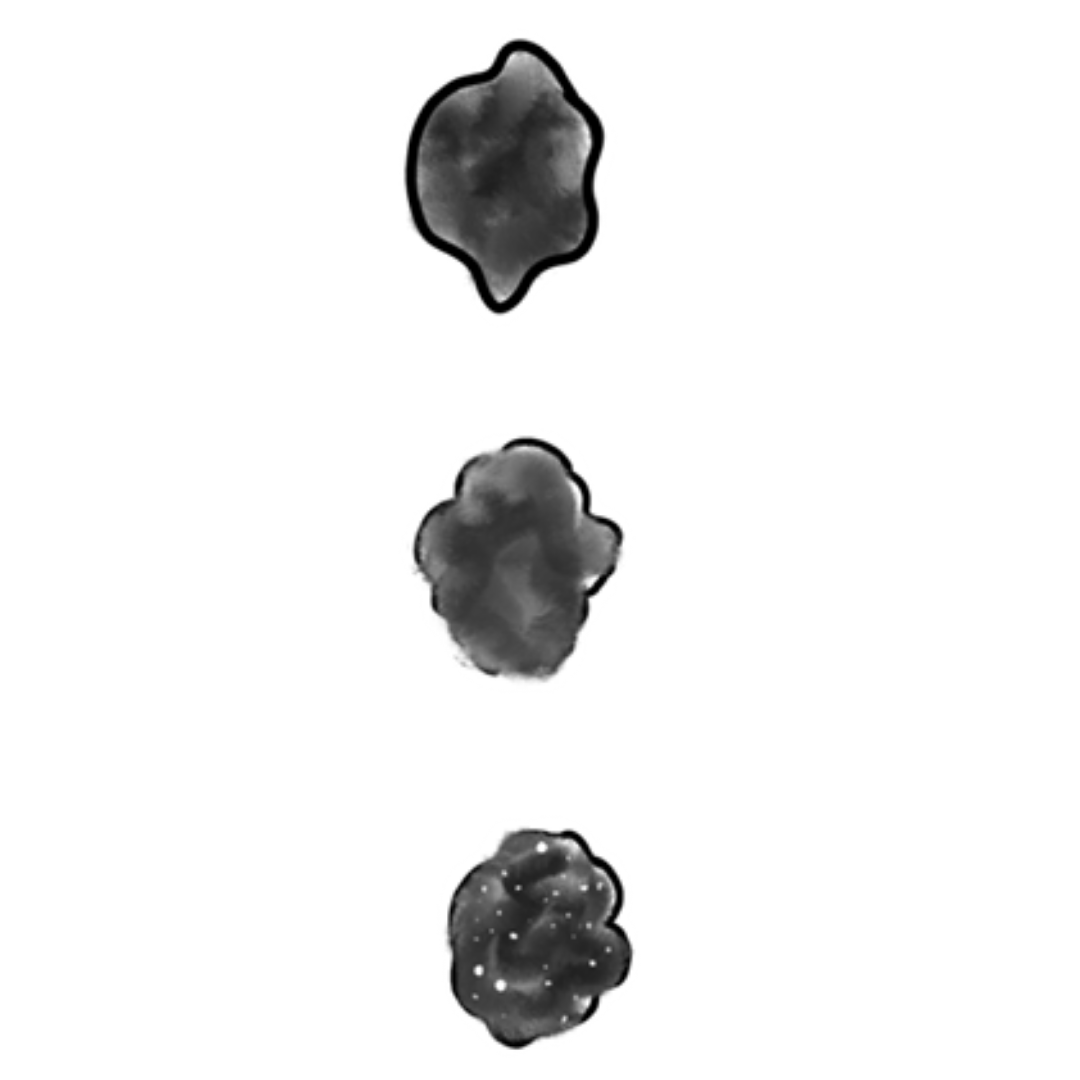

Hallazgos Ecográficos Lesión Tiroidea Maligna

Ecogenicidad: Sólido, hipoecogénico

Forma: más alto que ancho

Márgenes: irregulares o microlobulados

Microcalcificaciones o gruesas calcificaciones

Fig1. Esquema patrones malignos